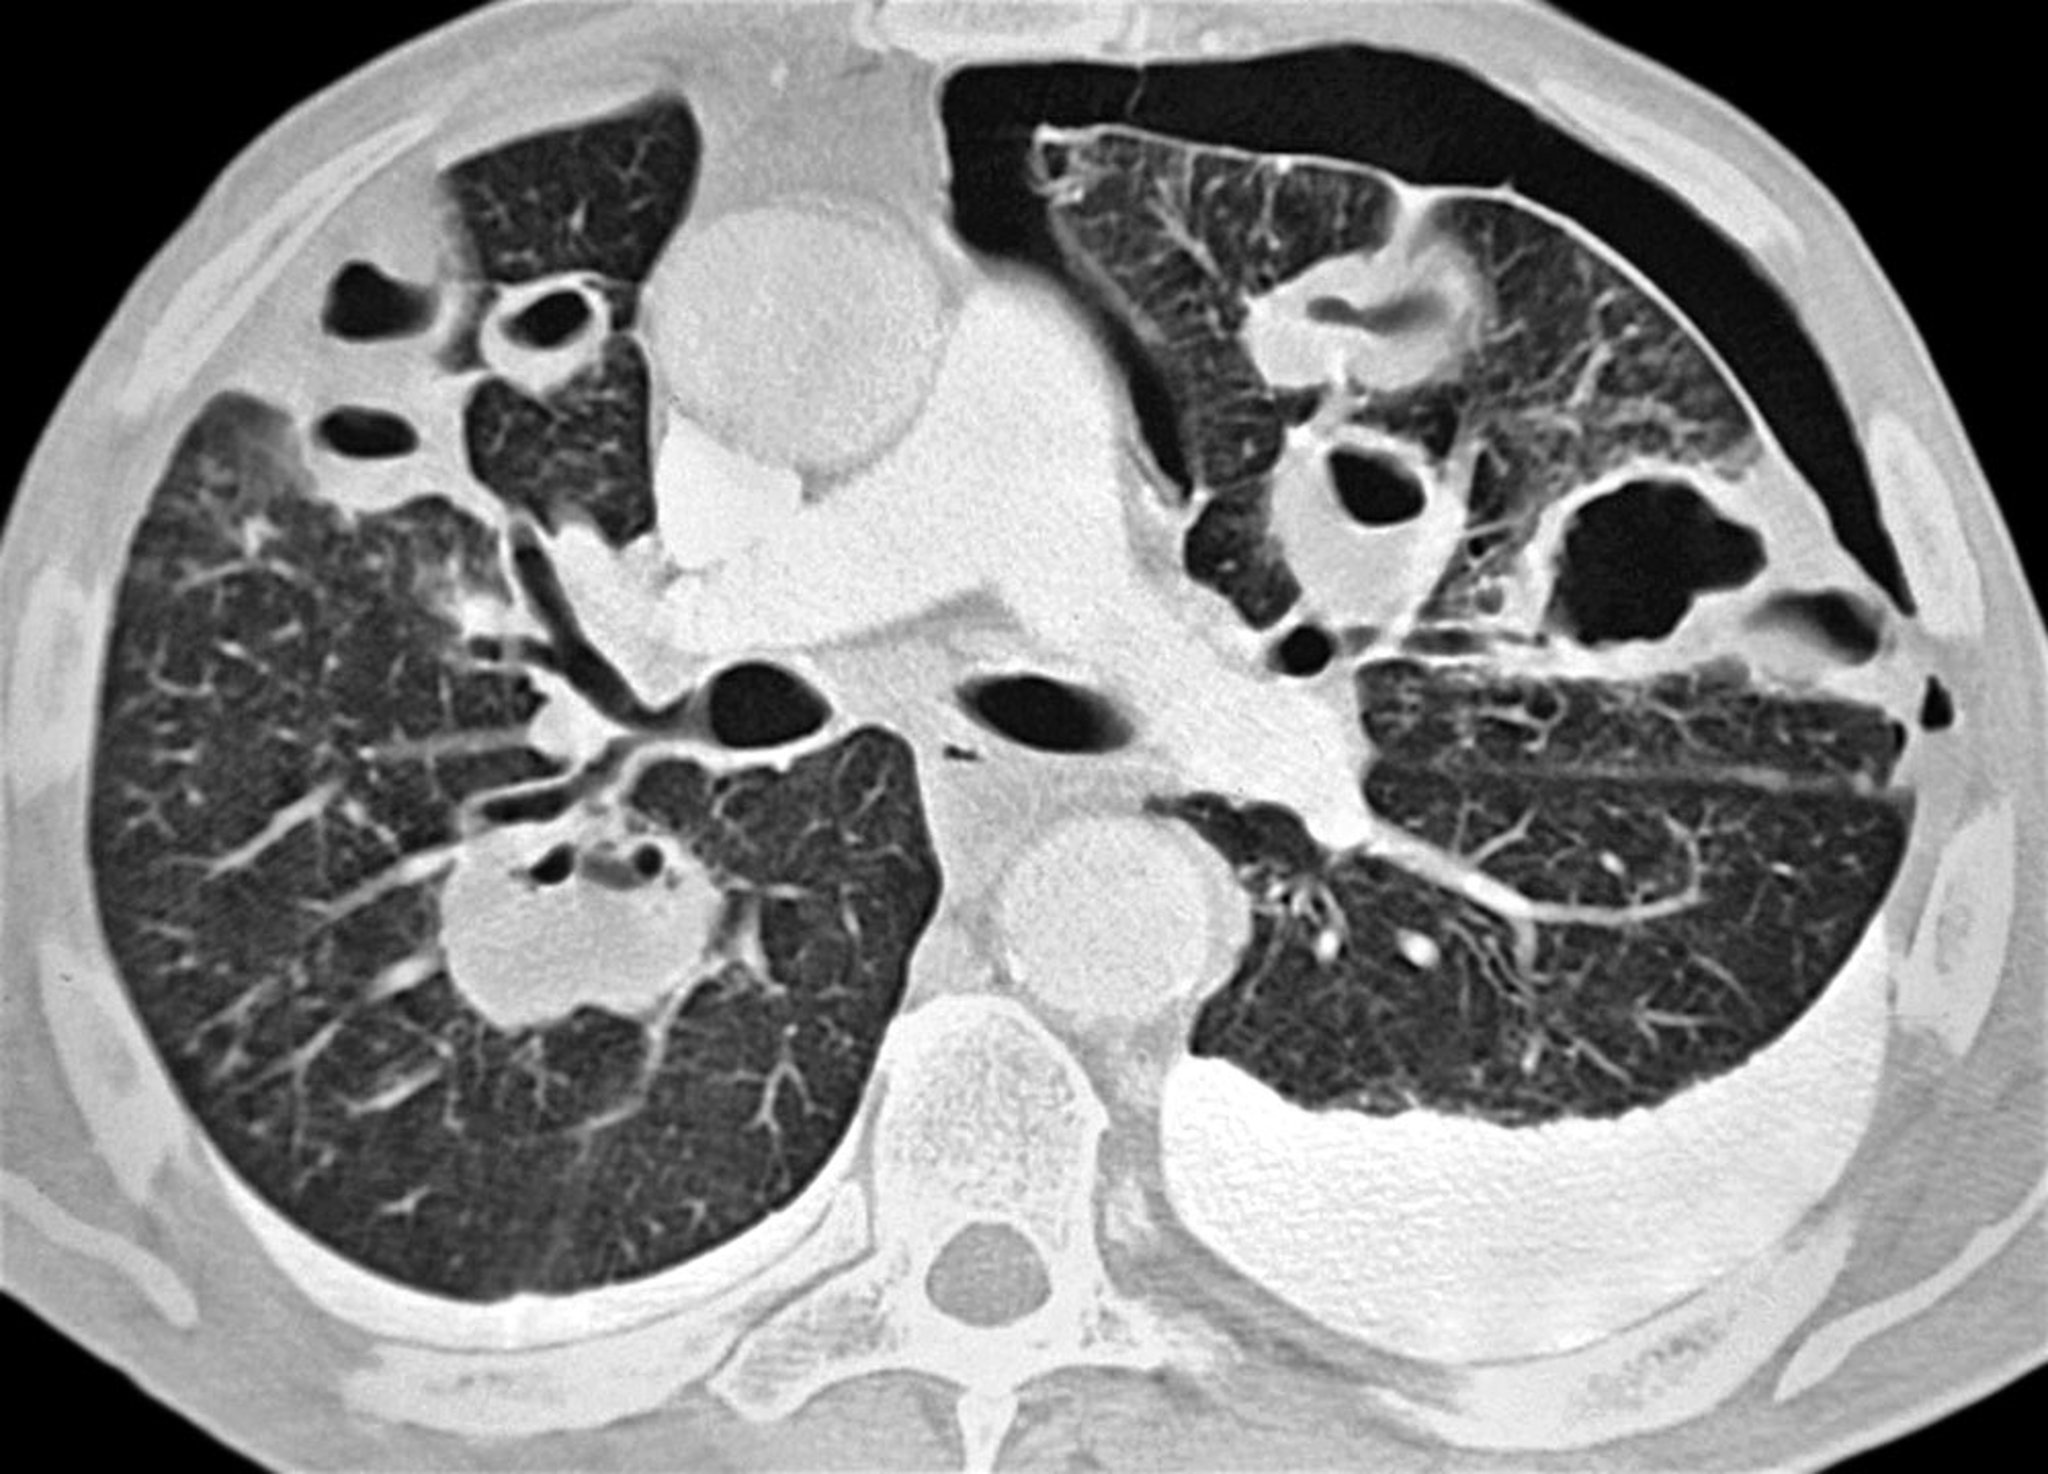

Pneumothorax (CT Scan)

This axial CT scan shows a left-sided pneumothorax in a patient with bacterial pneumonia. Multiple abscesses and bilateral pleural effusions (more prominent on the left) are seen as well.